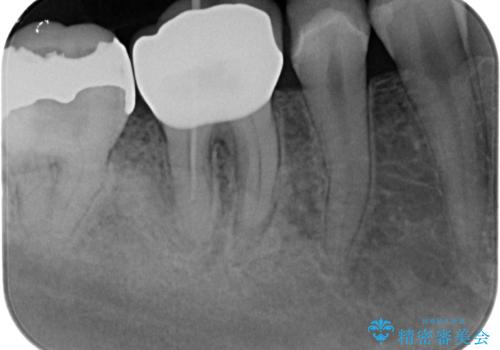

- メンテナンスで来院された患者様です。

歯茎が腫れたとの事で歯の神経が失活していたので精密根管治療を行い、ジルコニアクラウンで治療を行いました。

神経が失活しているので痛みは感じにくいですがこのまま放置をしてしまうと骨が溶けたり痛みが出たりします。